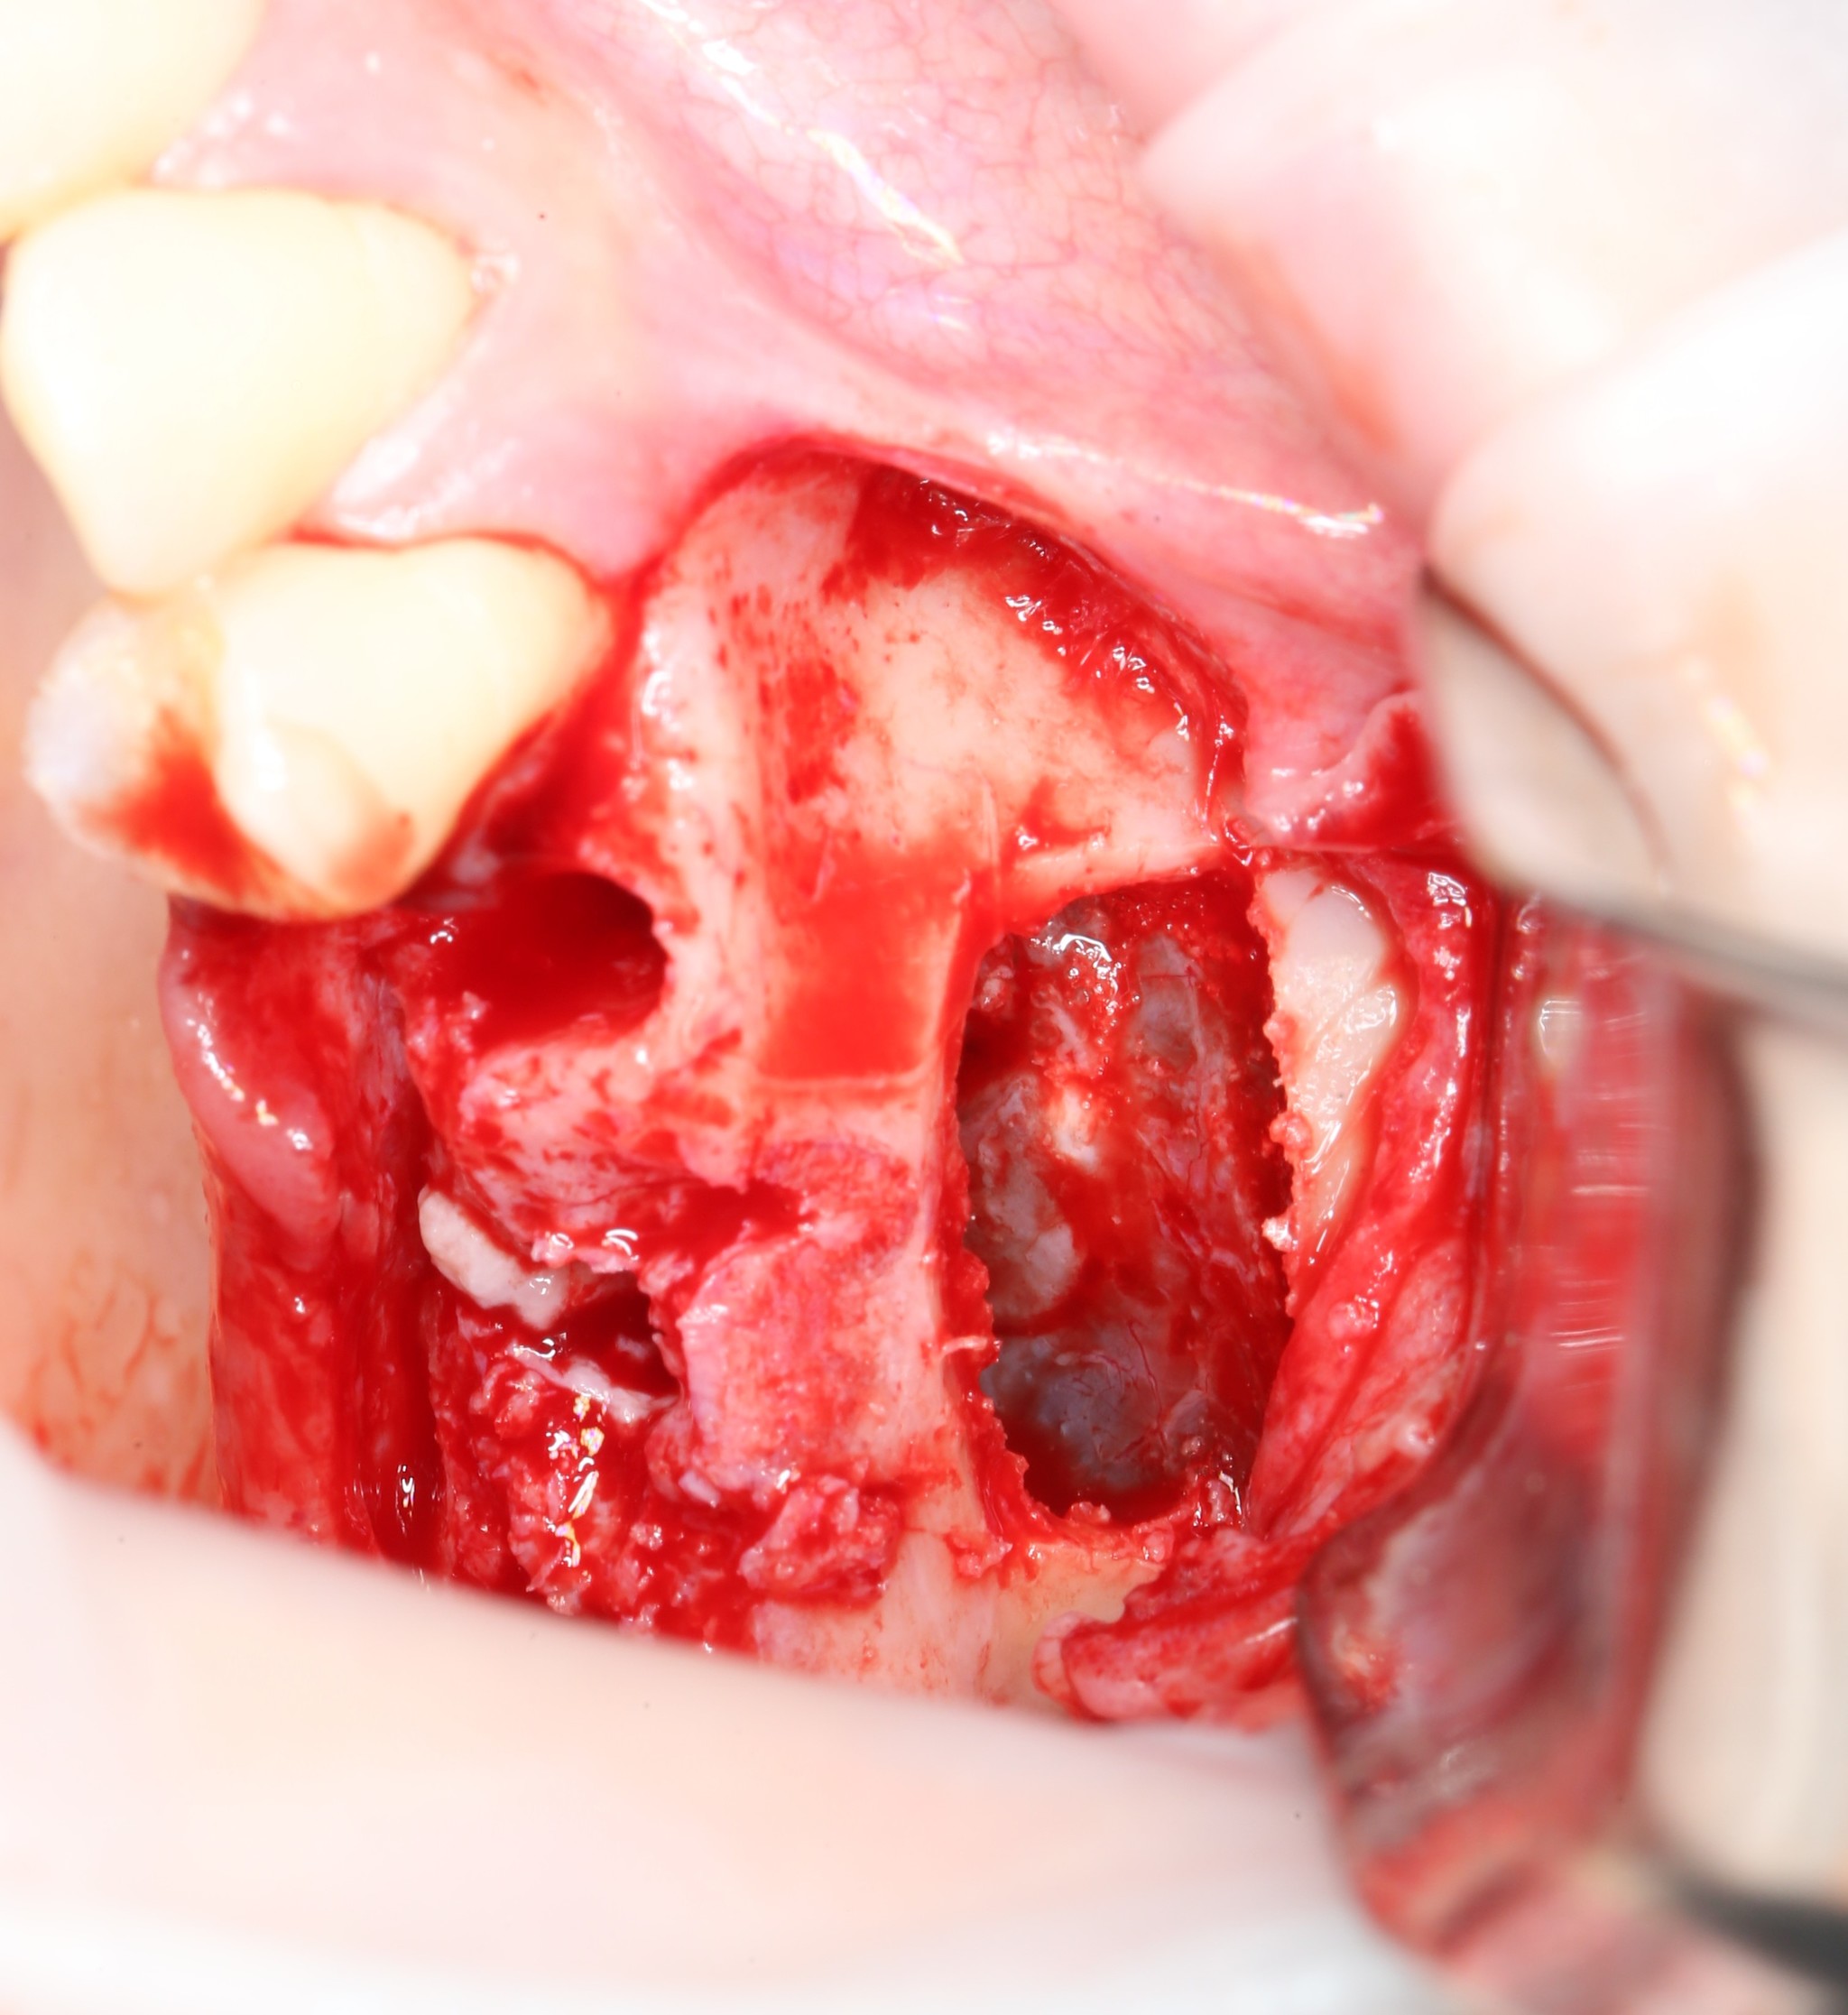

Далее укладывается дополнительная порция костного материала, а «окно» закрывается «крышкой», которая была вырезана ультразвуковым наконечником: